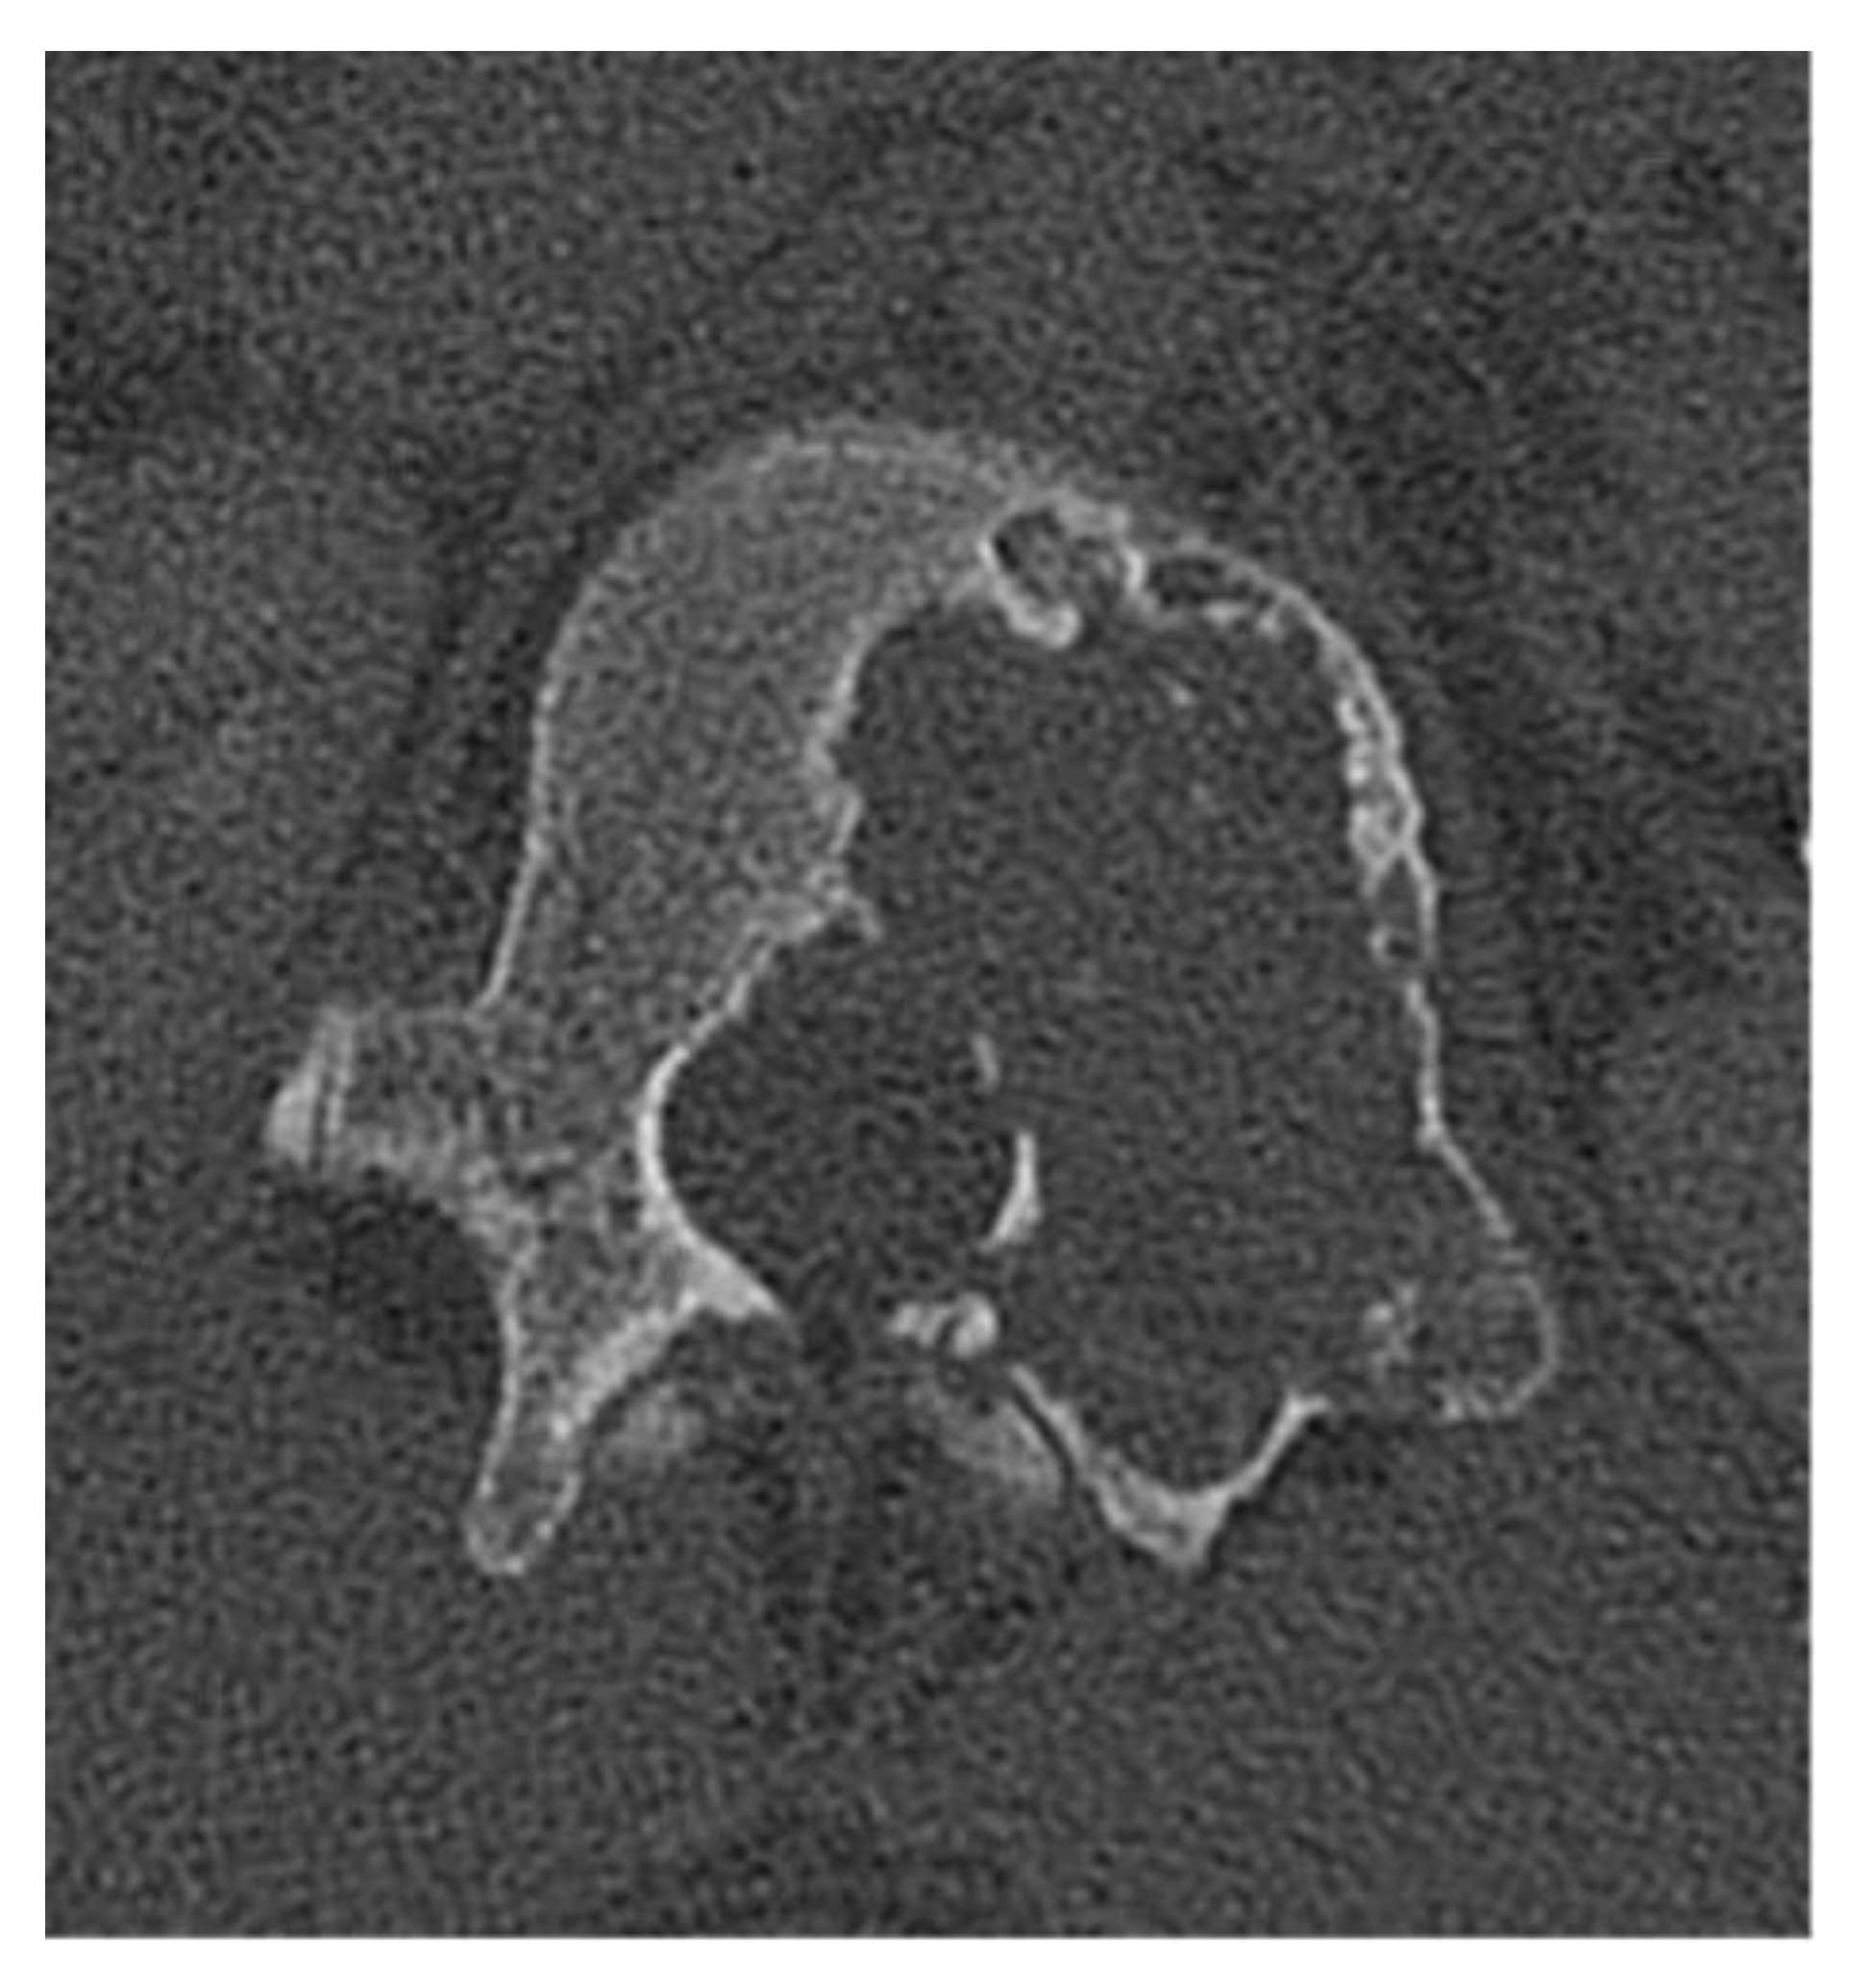

Paget Disease